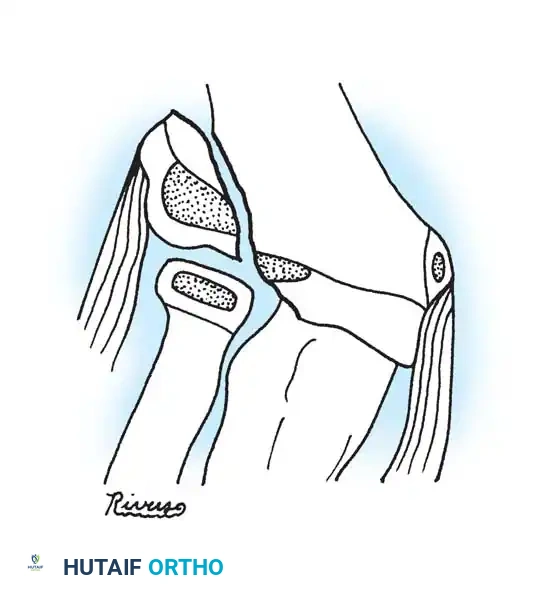

Fig. 33-43 Radial neck fracture in relation to arcade of Frohse.

Anatomical Pitfall: During percutaneous reduction, the Kirschner wire must be introduced on the ulnar side of the radius. Introducing the wire laterally risks iatrogenic injury to the deep branch of the radial nerve (posterior interosseous nerve) as it traverses the arcade of Frohse.

Fig. 33-44 A-D, Reduction of radial head by leverage method and retrograde intramedullary pinning with Kirschner wire.

- Reduction: The pin is rotated 180 degrees around its long axis. The bent tip acts as a cam, elevating the radial head and shifting it medially into anatomical position beneath the lateral condyle.

- Insertion: The wire is advanced retrograde through the medullary canal until the bent tip engages the displaced proximal epiphysis.

- Pin Preparation: A steel Kirschner wire or titanium elastic nail (TEN) is sharply bent at the distal 1.5 cm.

- Entry Point: A small incision is made over the distal lateral radial metaphysis, taking care to protect the superficial radial nerve.

The Metaizeau Technique (Elastic Stable Intramedullary Nailing)

Gonzalez-Herranz et al. and Metaizeau revolutionized the treatment of displaced radial neck fractures (O’Brien types II and III) using retrograde intramedullary pinning. This technique boasts excellent results in over 94% of cases.